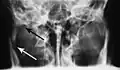

Towne's view of a bilateral condyle fracture. White arrow is a fracture on the neck of the condyle. Black arrow shows the condyle pulled to the medial. The same injury can be seen on the opposite side -